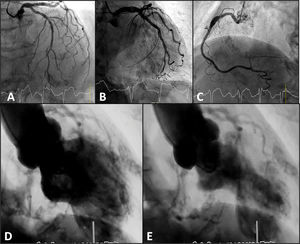

On the fifth day of hospitalization, the patient reported chest pain and the electrocardiogram showed atrial fibrillation with rapid ventricular response and ST-segment elevation in the anterolateral leads (Figure 1B). Emergent coronary angiography demonstrated absence of obstructive coronary lesions (Figure 2A-C; Videos 1-3) and ventriculography showed severe ventricular dysfunction with anterolateral, apical, and inferior dyskinesia and hypercontractility of the basal segments, compatible with Takotsubo syndrome (TTS) (Figure 2D and E; Video 4). At two-month follow-up, the patient remains asymptomatic and the echocardiogram demonstrated recovery of ventricular contractility.

Cardiac catheterization during primary percutaneous coronary intervention. (A-C) Coronary angiography with non-obstructive coronary artery disease; (D-E) ventriculography showing wall motion abnormalities in apical segments of the anterolateral and inferior walls, compatible with Takotsubo wall motion abnormality pattern.